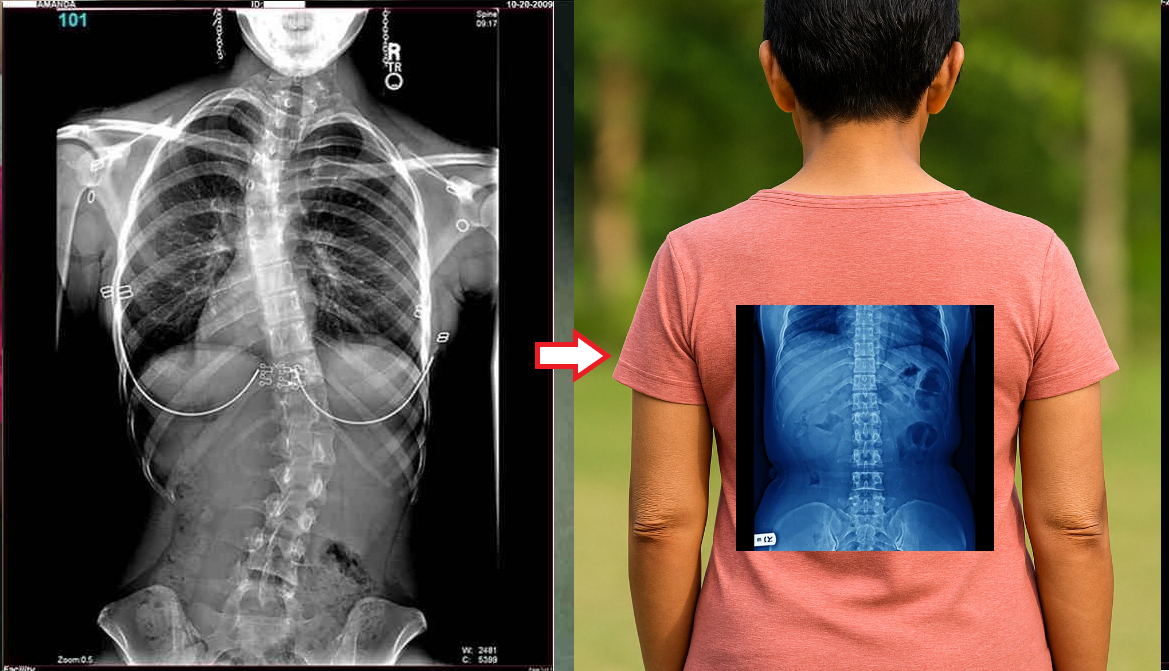

— Apakah Anda benar-benar berpikir bahwa pijat atau analgesik dapat mencegah kerusakan sendi dan tulang rawan? Itu adalah kesalahpahaman besar. Obat-obatan dari apotek tidak dapat meregenerasi jaringan, sementara bahan kimia yang terkandung di dalamnya justru merusak hati dan ginjal seiring waktu. Tubuh tidak dapat selamanya menanggung beban racun ini, dan alih-alih menyelesaikan masalah, Anda justru meracuni diri sendiri! Hal ini terutama berlaku untuk tulang belakang. Semua sendi mengalami keausan, tetapi pada tulang belakang, kurangnya ujung saraf dapat menyembunyikan perubahan yang berbahaya. Kompresi saraf skiatik akibat hernia adalah proses yang menyakitkan, awalnya menyebabkan nyeri ringan di punggung bawah, lalu menjalar ke kaki, menyebabkan kesemutan, mati rasa, dan akhirnya hilangnya fungsi kaki sepenuhnya. Kerusakan yang terus berkembang akan menyebabkan kelumpuhan pada bagian bawah tubuh, dan mengembalikan kendali atasnya menjadi hampir tidak mungkin. Lihat gambar ini. Ini adalah kondisi tulang belakang seseorang yang baru berusia 44 tahun, tetapi tampak seperti lansia. Dulu, kerusakan seperti ini hanya terjadi setelah usia 60 tahun, tetapi sekarang hal ini menjadi umum bagi mereka yang baru saja melewati usia 40 tahun. Kerusakan ini akan terus berkembang seiring bertambahnya usia, dan mengabaikannya berarti menempatkan diri dalam risiko kelumpuhan total!

Tulang belakang pasien berusia 44 tahun: semuanya dimulai dengan nyeri ringan, tetapi hanya dalam satu minggu muncul hernia, dan dalam dua minggu terjadi pergeseran tulang belakang, tekanan pada saraf, dan akhirnya—kursi roda.

Lihat foto-foto ini. Inilah yang terjadi pada mereka yang tidak memperhatikan gejala. Hari ini, mereka adalah orang-orang yang tak berdaya, dan banyak di antara mereka tidak memiliki siapa pun untuk membantu. Apakah Anda menginginkan nasib seperti itu?

Wanita, 52 tahun. Pergeseran parah dan deformasi cakram tulang belakang dengan kompresi saraf serta kerusakan sumsum tulang belakang.